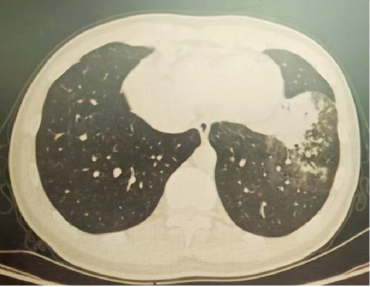

以上是他的胸部CT影像,主要表现为左下肺炎症,片絮影+磨玻璃影。

肺部感染的影像学特征

多发性结节伴快速进展

CT表现为双肺多发实性结节(直径0.5-3cm),结节边缘可见毛刺征及分叶征,特征性表现为短期内体积呈几何级数增长(如1周内增大10倍),需与转移瘤、结核球等鉴别。

混合性密度影与胸腔积液

40%病例出现磨玻璃影与实变影共存,部分结节中央可见液化坏死;30%伴单侧渗出性胸腔积液,积液分析呈渗出性但培养阴性,此表现易误诊为脓胸。